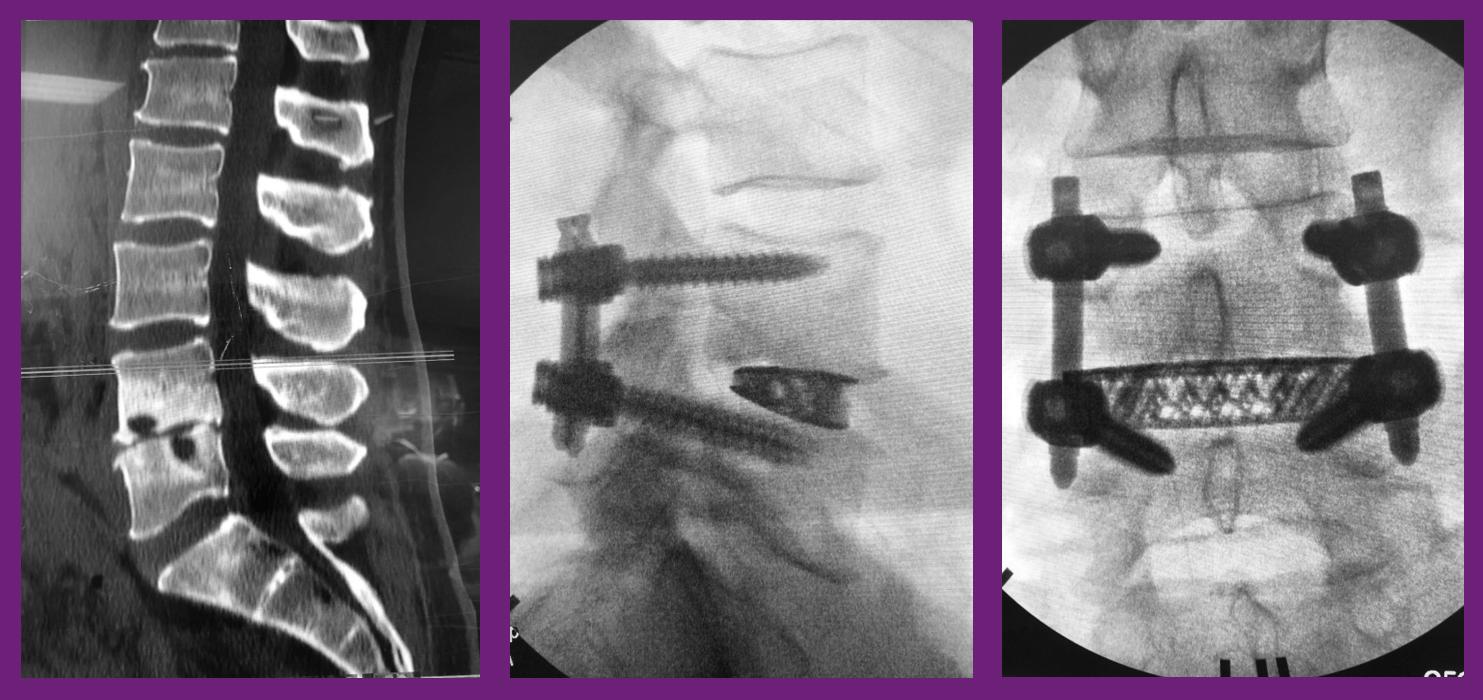

From www.ijssurgery.com

Multilevel extreme lateral interbody fusion (XLIF) and osteotomies for 3dimensional severe Pain After Xlif Surgery Learn what psoas muscle pain is, how it affects your recovery after xlif surgery, and how to alleviate it with rest, ice, stretching,. Pseudoarthrosis may go undetected or lead to a. In general, xlif surgical recovery may include: Postoperative care for spinal fusion surgery. Learn what to expect after an extreme lateral interbody fusion (xlif) surgery, including pain management, activity. Pain After Xlif Surgery.

Multilevel extreme lateral interbody fusion (XLIF) and osteotomies for 3dimensional severe Pain After Xlif Surgery In general, xlif surgical recovery may include: Learn what to expect after an extreme lateral interbody fusion (xlif) surgery, including pain management, activity limitations. Learn what psoas muscle pain is, how it affects your recovery after xlif surgery, and how to alleviate it with rest, ice, stretching,. Pain is likely to continue to decrease gradually, but some patients continue to. Pain After Xlif Surgery.